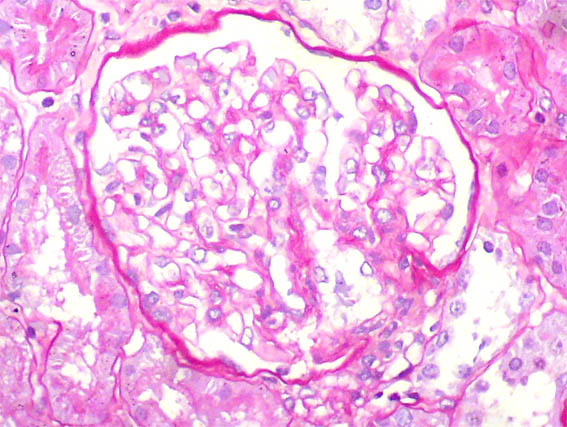

Figure 4. PAS, X400.